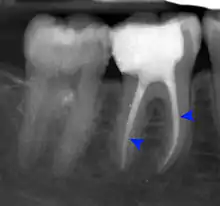

The periodontal ligament becomes inflamed and there may be pain when biting or tapping on the tooth. On an X-ray, bone resorption appears as a radiolucent area around the end of the root, although this does not manifest immediately.[10]: 228 Acute apical periodontitis is characterized by well-localized, spontaneous, persistent, moderate to severe pain.[6]: 125–135 The alveolar process may be tender to palpation over the roots. The tooth may be raised in the socket and feel more prominent than the adjacent teeth.[6]: 125–135

- Radiographs utilized to find dental caries and bone loss laterally or at the apex.

Decay (green) with apical abscess (blue)